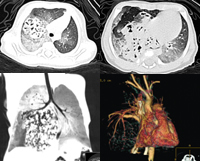

图1、2 CT轴位平扫,肺窗:可见上下肺野分布外形不规则团块状占位,其内见弥漫泡状低密度影;病变主要分布于右上肺尖段,右侧前下胸膜下及右下肺后内侧脊柱前(箭头所示)

图3 CT二维冠状位重建:右主支气管受压上移 ,其上下方均可见占位病变

图4 CT三维重建:心影纵隔受压向左移,右侧肺、动静脉受压上抬, http://www.100md.com